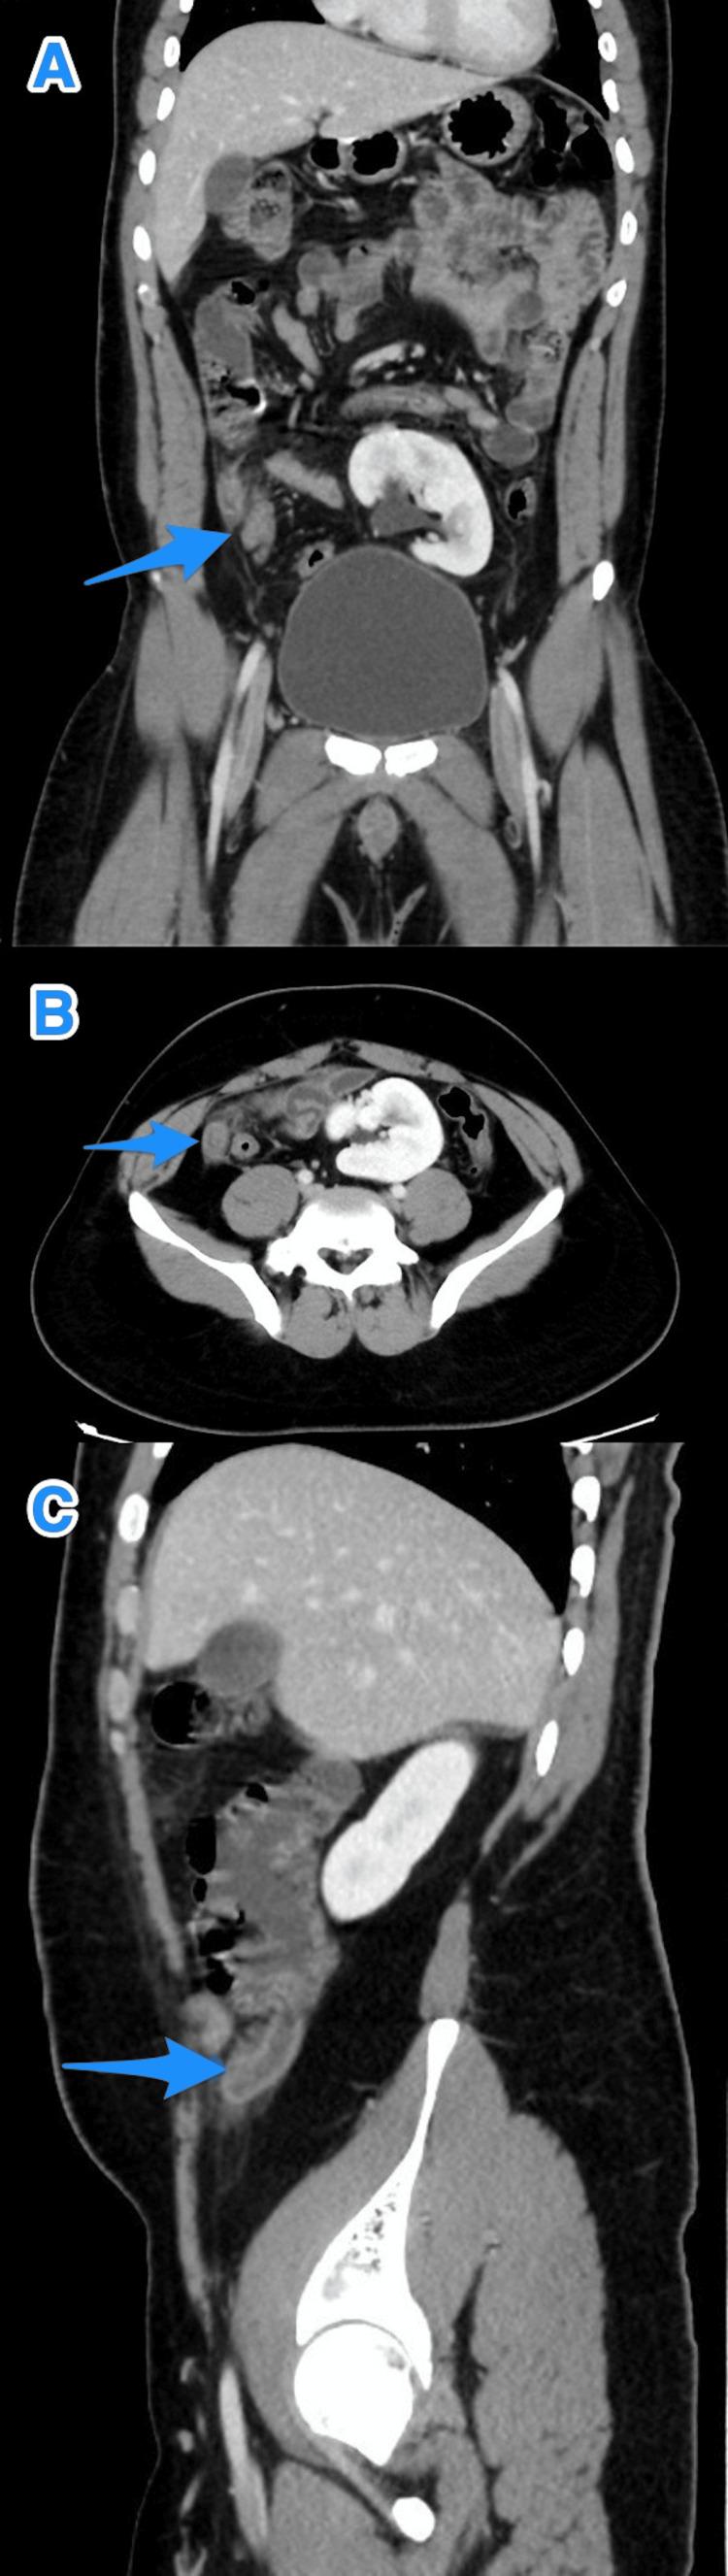

Appendicular diverticulitis (AD) is a rare entity characterized by the inflammation of the arising diverticulum of the appendix. It has been reported to carry a high risk of perioperative complications, such as bleeding and perforation. Furthermore, multiple articles have highlighted the importance of diagnosing AD early due to its strong association with malignancies. Limited published cases concerning AD in our country and globally are available in the literature. Hence, we present in this article a case series of five exciting cases of incidental findings of AD that were initially diagnosed as acute appendicitis based on clinical evaluation and imaging findings. In our series, we performed a retrograde evaluation of the computed tomography scans of all five cases that showed diverticula. In conclusion, histopathological evaluation remains the method of choice to reach the definitive diagnosis; however, it is essential to highlight the relevance of imaging in diagnosing AD preoperatively in the early stages to reduce morbidity and mortality.